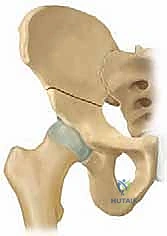

جراحة قطع عظم الحوض الثلاثي (TIO) هي إجراء جراحي يعيد توجيه التجويف الحقي لتحسين تغطية رأس الفخذ وعلاج خلل تنسج الورك، خاصة في الأطفال والمراهقين. يتم من خلال قطع عظام الحوض الثلاثة (الحرقفة، الإسك، العانة) لتمكين دوران التجويف الحقي حول رأس الفخذ، مما يزيد من استقراره ويقلل من خطر التهاب المفاصل المبكر.

من خلال إجراء قطوع دقيقة في عظام الحوض الثلاثة (الحرقفة، الإسك، العانة)، يتم تحرير التجويف الحقي بالكامل ليتم تدويره حول رأس الفخذ، مما يضمن استقراراً ميكانيكياً حيوياً للمفصل، ويمنع الخلع المتكرر، ويقي المريض من خطر الإصابة بالفصال العظمي (التهاب المفاصل التنكسي) المبكر الذي قد يستدعي زراعة مفصل صناعي في سن مبكرة.

بمجرد اكتمال هذه القطوع الثلاثة، يصبح التجويف الحقي (الكوب) منفصلاً تماماً عن بقية الحوض، مع بقاء إمداداته الدموية سليمة.

4. إعادة التوجيه والتدوير (Rotation & Redirection)

باستخدام أدوات خاصة، يقوم الدكتور هطيف بتدوير التجويف الحقي الحر في ثلاثة أبعاد (للأمام، وللخارج، وللأسفل) حتى يغطي رأس عظم الفخذ بشكل مثالي وميكانيكي سليم. يتم التحقق من الزاوية الجديدة فوراً داخل غرفة العمليات باستخدام جهاز الأشعة السينية المتحرك (C-arm).

5. التثبيت القوي (Fixation)

بمجرد الوصول إلى الوضع المثالي، يتم تثبيت العظام في مكانها الجديد باستخدام براغي معدنية قوية من التيتانيوم أو دبابيس (K-wires). هذا التثبيت يضمن التحام العظام بشكل صحيح خلال فترة التعافي.